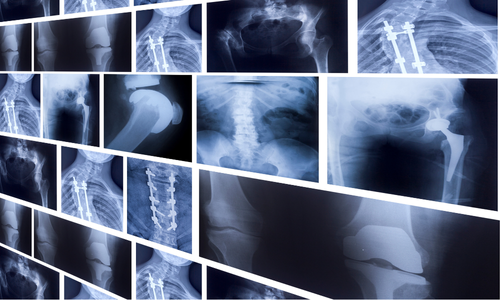

河村クリニックの整形外科では、骨・関節・筋肉・神経などの運動器疾患に幅広く対応しています。

レントゲン検査で状態を確認し、固定・包帯・リハビリなど最適な治療を行います。